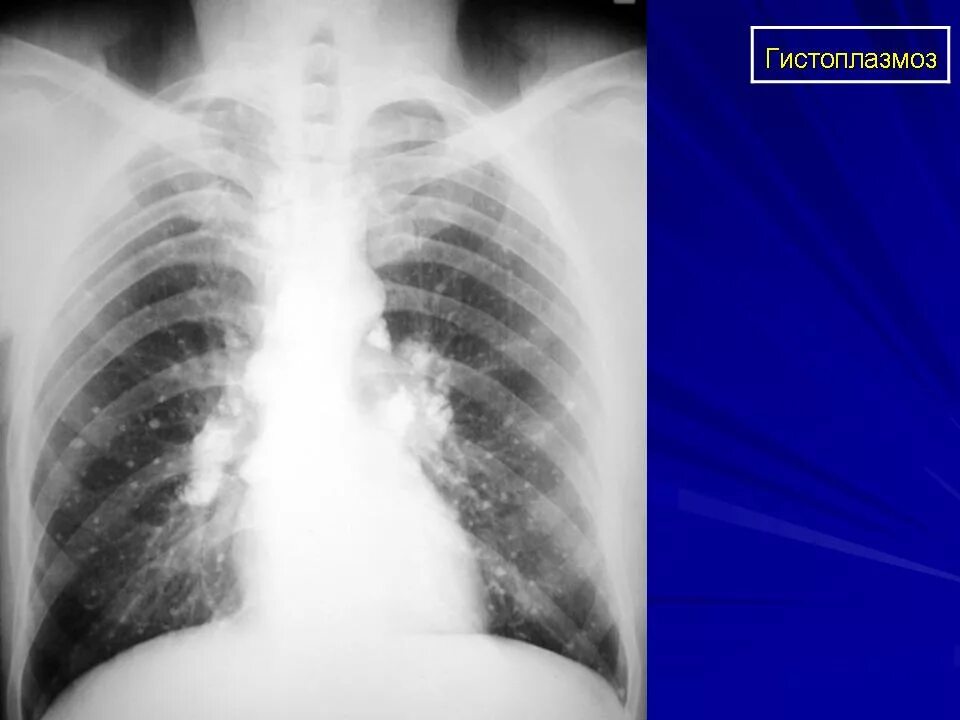

Гистоплазмоз это